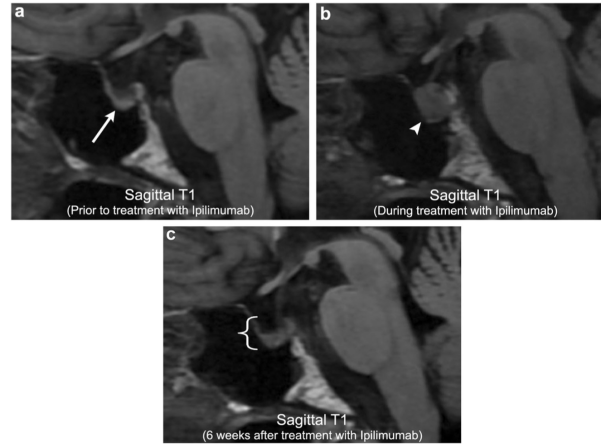

另一個常見的與化療相關(guān)的并發(fā)癥討論是伊匹單抗(ipilimumab)性垂體炎。伊匹單抗(Ipilimumab)(MDX-010)是一種單克隆抗體,其作用原理是控制細胞毒性T淋巴細胞相關(guān)抗原4,增強病人的免疫系統(tǒng)以產(chǎn)生對惡性腫瘤細胞的反應(yīng)。這個藥物特別對轉(zhuǎn)移性黑色素瘤和腎細胞癌合適,現(xiàn)在被廣泛用于出現(xiàn)疾病播散的患者。然而,增強免疫反應(yīng)可以對全身引起許多不良的自身免疫反應(yīng),如結(jié)腸炎,皮炎,和關(guān)節(jié)炎,等等。

在中樞神經(jīng)系統(tǒng),文獻中伊匹單抗(ipilimumab)誘發(fā)的垂體炎是比較好辨識的自身免疫反應(yīng)。盡管有認(rèn)為只發(fā)生在小于5%的接受伊匹單抗治療的患者。這些患者臨床上可表現(xiàn)為威脅到生命的激素失調(diào),特別是高皮質(zhì)醇激素增多癥。在影像學(xué)上,伊匹單抗誘發(fā)的垂體炎導(dǎo)致彌漫性垂體的增大,常為T1加權(quán)成像低信號,漏斗部增厚/增大。停用伊匹單抗后隨訪影像和類固醇的引入使用后典型的表現(xiàn)為異常發(fā)現(xiàn)的完全消失與垂體復(fù)原到基線外。這種影像上的好轉(zhuǎn)與臨床上的癥狀和激素水平的變化好轉(zhuǎn)相一致。重要的是,許多患者會繼續(xù)進展出現(xiàn)不同程度的垂體功能減退,需要激素替代性治療。

案例1:伊匹單抗引起的垂體炎

63歲男性,轉(zhuǎn)移性黑色素瘤患者。初始的影像顯示部分空蝶鞍與其他方面正常的垂體腺(箭頭)。開始伊匹單抗治療后,有標(biāo)記異質(zhì)性增大的垂體(箭頭)同時伴有伊匹單抗引起的垂體炎。中止伊匹單抗治療后6周的影響顯示垂體的增大豪裝(括號)。然而,病人當(dāng)時出現(xiàn)全垂體功能低下。